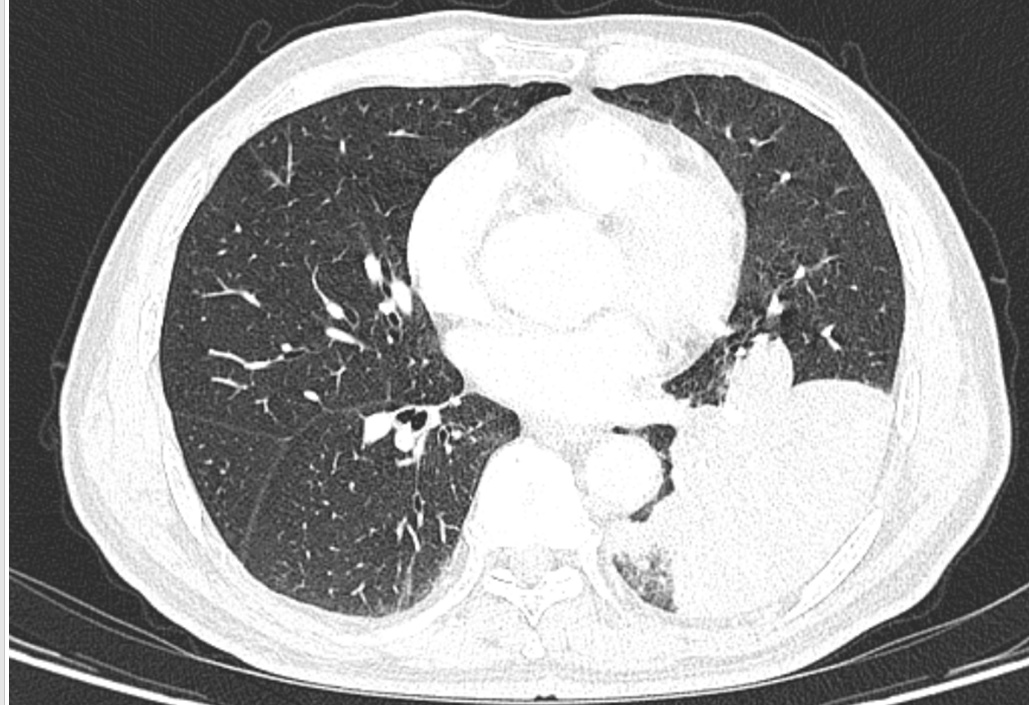

然而,从那天起,李老伯的咳嗽次数明显增多,而且还伴有浓痰,家人便带着李老伯到南京市第一医院河西院区呼吸与危重症医学科门诊就诊。胸部CT结果显示李老伯左肺下叶出现了一片“占位性病变”!

入院后,医生敏锐捕捉到一个关键细节:李老伯既往有明确的饮食后呛咳史,且此次发病前有吃鱼后呛咳的经历。因此判断,这应该不是肺部感染或肿瘤,高度怀疑是气道异物,要对李老伯进行支气管镜检查!

竟意外发现在一片因炎症而充血水肿的支气管黏膜中,一个细长、坚硬的异物正死死地卡在管腔内,周围包裹着大量的脓性分泌物。

原来竟然是一块长约1.6厘米的鱼骨!至此,真相大白。所谓的“肺部占位”,正是因为这块鱼骨堵塞气道,引发了堵塞性肺炎和肺不张,导致李老伯长达半个月的咳嗽和咳浓痰。